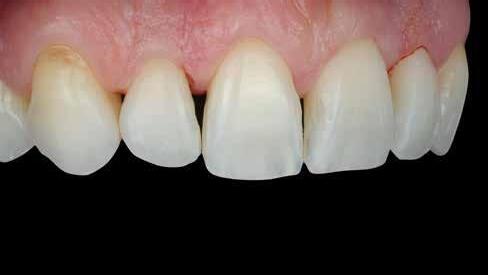

A fogászati kezelések során manapság már nem kizárólag az esztétikai megjelenés helyreállítására törekszünk. Sokszor a kedvezőtlen esztétikai megjelenés hátterében álló okok következményes módon a fogazat funkcionális működését is károsítják, így a kezelések során ezeknek a helyreállításával is foglalkoznunk kell. A különböző funkcionális és esztétikai diszkrepanciák kezelésére számtalan módszer létezik, ám ezen fogászati beavatkozások mindegyikében közös, hogy a kivitelezésük során nagyon szoros együttműködésre van szükség a kezelést végző fogorvos és a munkáját segítő fogtechnikus között. Az alábbi esetbemutatás során egy fiatal hölgypáciens fogazatának héjak alkalmazásával történő esztétikai és funkcionális rehabilitációját szeretnénk ismertetni.

Esetbemutatás

A 19 éves hölgypáciens azzal a kéréssel jelentkezett a rendelőnkbe, hogy szebb fogakat szeretne. Az első konzultáció alkalmával megkérdeztük, hogy mi zavarja leginkább a fogazatának jelenlegi megjelenésében, valamint azt is megbeszéltük vele, hogy milyen végeredmény elérése esetén lenne maradéktalanul elégedett. Ebben az esetben a kezelési célokat az alábbiakban határoztuk meg:

A páciens fogazata esztétikai megjelenésének és funkcionális működésének a lehető legtöbb, saját foganyag megtartása mellett történő helyreállítása (1. és 3. ábra). A lehető legideálisabb esztétikai végeredmény elérése érdekében néhány esetben a fogak alakjának módosítá -

sára is szükség van (2. és 4. ábra).

A kezelés megtervezése során kifejezett jelentősége van annak, hogy jó kommunikáció legyen a páciens, a fogorvos és a fogtechnikus között. A páciens leendő fogazatának természetes megjelenését a kezelésben részt vevő team szakmai felkészültsége, gyakorlati tapasztalata és a kezelés sikerességének irányába történő elkötelezettsége biztosítja. A beavatkozások megkezdése előtt megtörtént a páciens anamnézisének a felvétele, valamint a klinikai kivizsgálását is elvégeztük. Ezt követően lenyomatokat készítettünk a kiindulási állapotról, majd a kiindulási helyzetet extra- és intraorális fotók segítségével is rögzítettük (13. a-c. ábra).

A cikkünkben bemutatásra kerülő eset ellátása során preparációt héjak készre vitele során a platinafólia technikát alkalmaztuk.

kívül vékonyak, és ezáltal a végleges rögzítésük előtt jelentős olyan minimál invazív kezelési eljárásnak számítanak, amely

elérni. A fent leírtak alapján bátran

preparációt nem igénylő héjak készítése mellett döntöttünk. A alkalmaztuk. Annak ellenére, hogy az elkészítésre kerülő héjak rendjelentős törésveszéllyel állunk szemben, összességében mégis amely segítségével kifogástalan esztétikai eredményeket lehet javasoljuk e módszer alkalmazását.